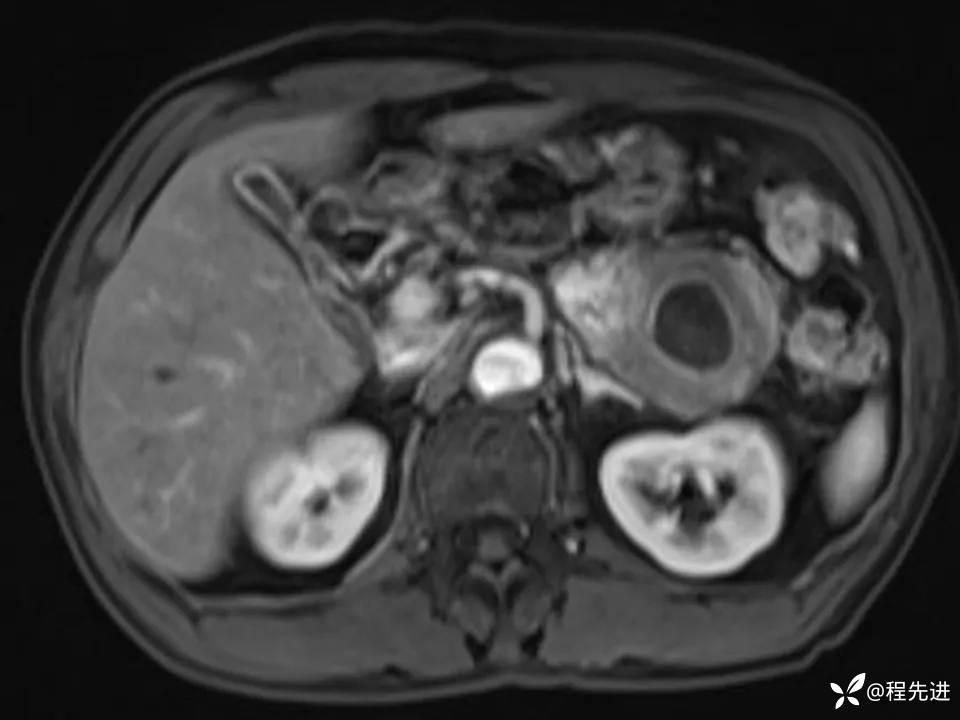

患者性别:男

患者年龄:61岁

简要病史:体检发现胰腺占位

MRI平扫+增强: